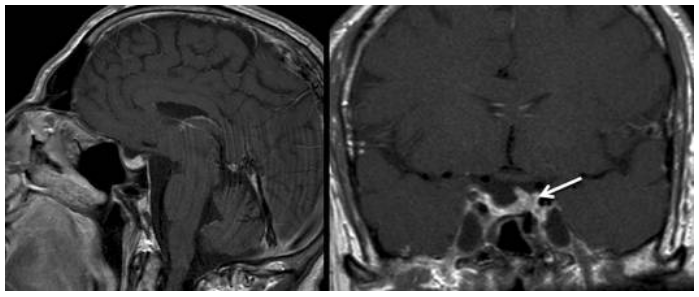

MRI影像

性欲減退、勃起功能障礙……54歲的約翰沒想到害怕的這些來的這么快。本以為只是年紀大了,沒想到看東西視野也開始變小。內(nèi)分泌學檢查發(fā)現(xiàn)生長激素和促性腺激素存在部分功能減退,核磁共振成像顯示鞍內(nèi)及鞍上存在一個均勻強化的病灶。由于腫瘤體積較大,視交叉已被明顯抬起且呈扁平狀。垂體及垂體柄向左側(cè)移位。綜合所有檢查結(jié)果,懷疑為無功能性垂體腺瘤。

術(shù)前影像